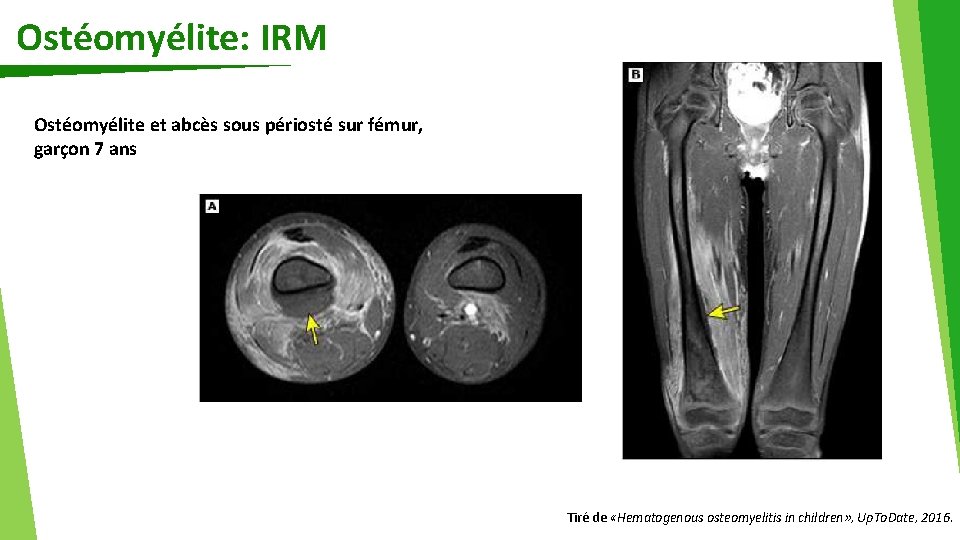

Ostéomyélite: IRM Ostéomyélite et abcès sous périosté sur fémur, garçon 7 ans Tiré de «Hematogenous osteomyelitis in children» , Up. To. Date, 2016.